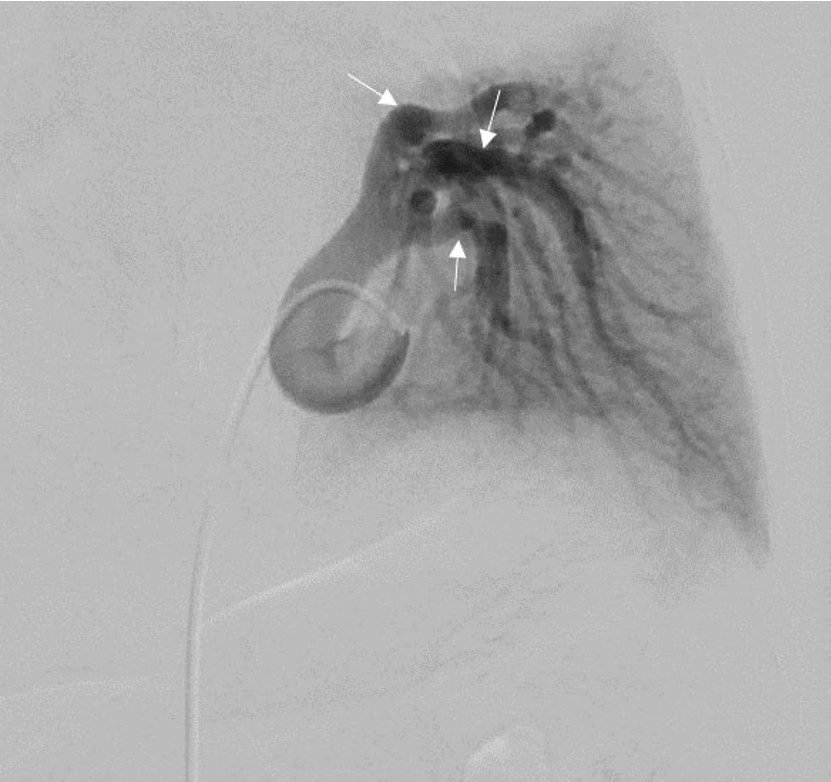

To confirm the diagnosis and exclude arteriovenous malformation, digital subtraction angiography (DSA) was performed (Figure 4). The DSA findings were consistent with the CT findings, and the aberrant branches were embolized with coils. The primary aberrant systemic artery, measuring 6.6 mm in its proximal segment, was occluded with an Amplatzer Vascular Plug, effectively terminating the aberrant arterial supply (Figure 5). No complications were observed during a 7-month follow-up period.